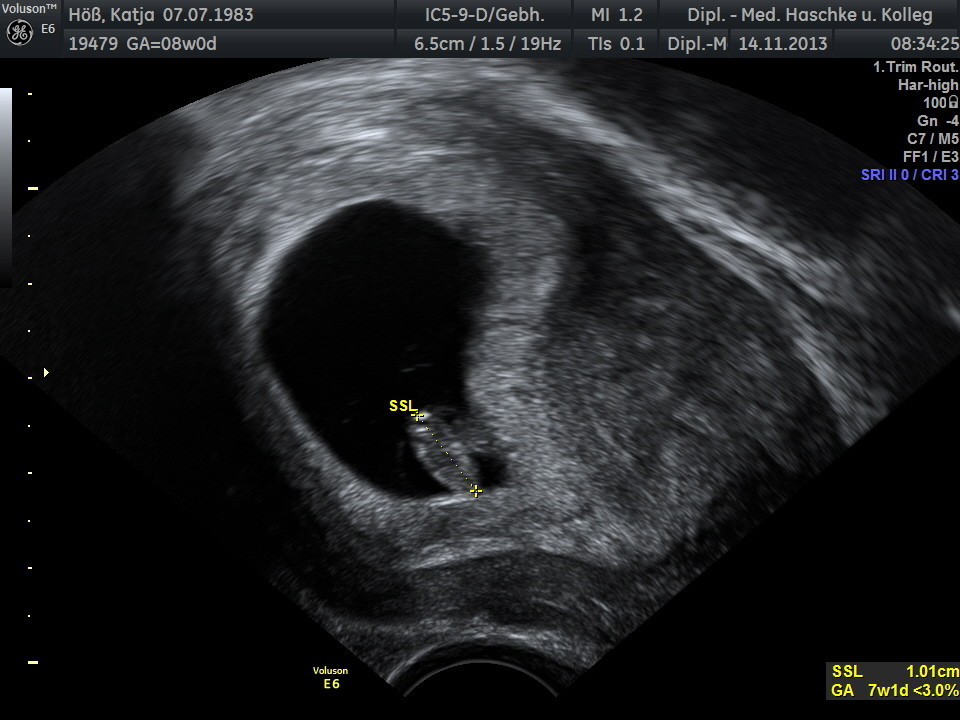

Schwangerschaftswoche 8

Das erste Ultraschallbild mit Herzschlag, wir waren mehr als glücklich und vor Freude flossen auch ein paar Tränen.